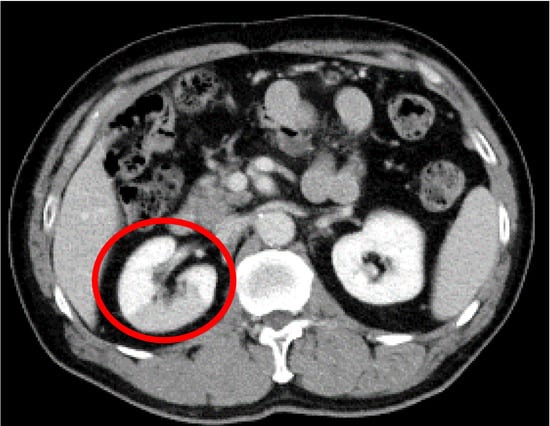

Asymptomatic Idiopathic Renal Infarction Detected Incidentally on Contrast-Enhanced Computed Tomography: A Case Report

2. Case Presentation